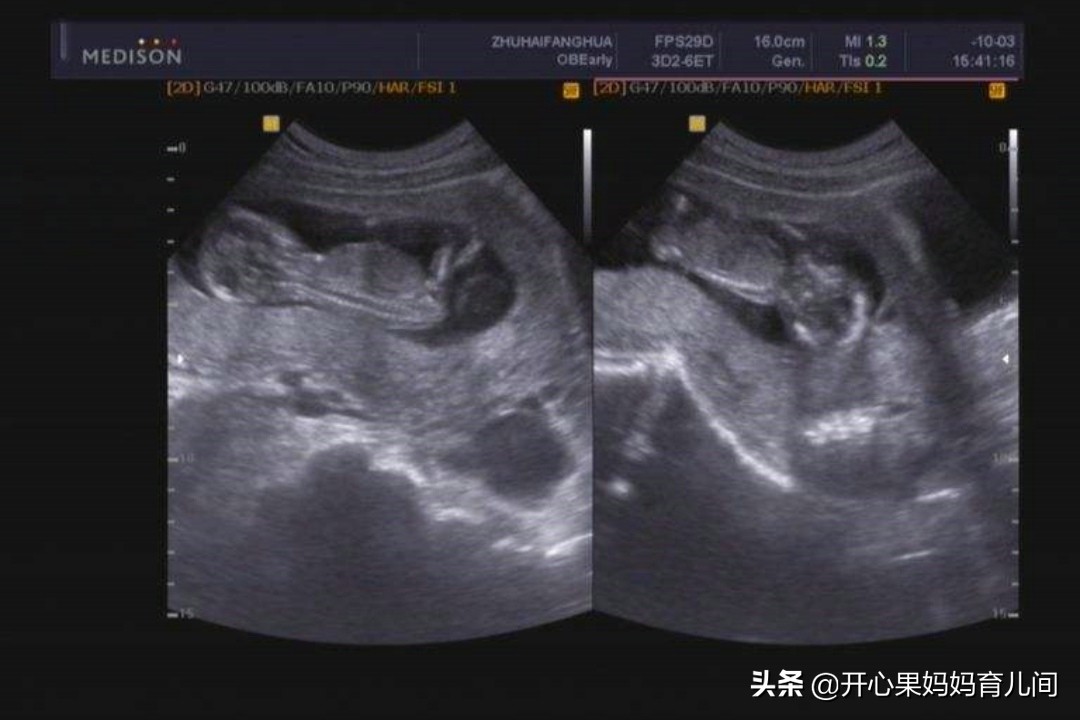

26周胎盘成熟度高达2级?

开心果妈妈在孕24周的时候,去市里医院检查四维,排在开心果妈妈前面的一个女生,是26周多几天。只听到房间内,医生对那位女生说:"你现在才26周多点儿,胎盘成熟度已经高达两级,你要稍微多注意一点了,否则容易早产。"

胎盘等级划分

10周到20周,胎盘等级:0级;

20到36周,胎盘等级:一级;

36到40周,胎盘等级:二级;

40周附近,胎盘等级:二级到三级。

从等级上来说,胎盘成熟度达到二级,就代表胎儿已经相对成熟了。胎盘等级达到三级,这代表胎盘已经成熟,可能正在走向老化。